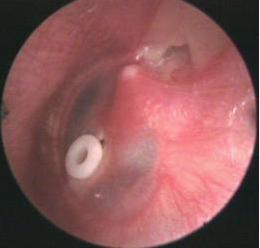

(3)鼓室置管术: 长期不愈或反复发作者,鼓室积液清除后,可经鼓膜留置通气管于鼓室内,以改善通气引流,有利于恢复咽鼓管功能。详细治疗方案可拨打免费医生电话029-87401000

中耳炎鼓室置管

通气管留置时间一般为6—8周,长可达半年至一年。待咽鼓管功能恢复后,通气管常自行排出于外耳道内。另外,紫外线或超短波,激光照射等物理疗法,可改善中耳血液循环,促进积液吸收。